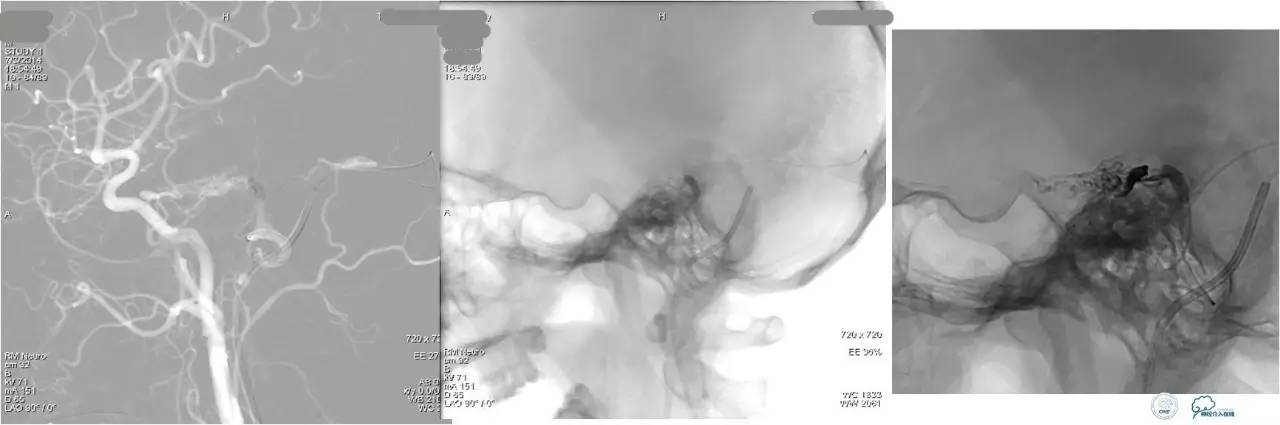

小脑幕缘区DAVF,只有颈外动脉参与供血,供血支细小。

选择抑制血管栓塞,胶无法弥散进入瘘口,选择另一支血管,近端防止Hyperform球囊。

最终胶弥散结果,瘘口完全消失。